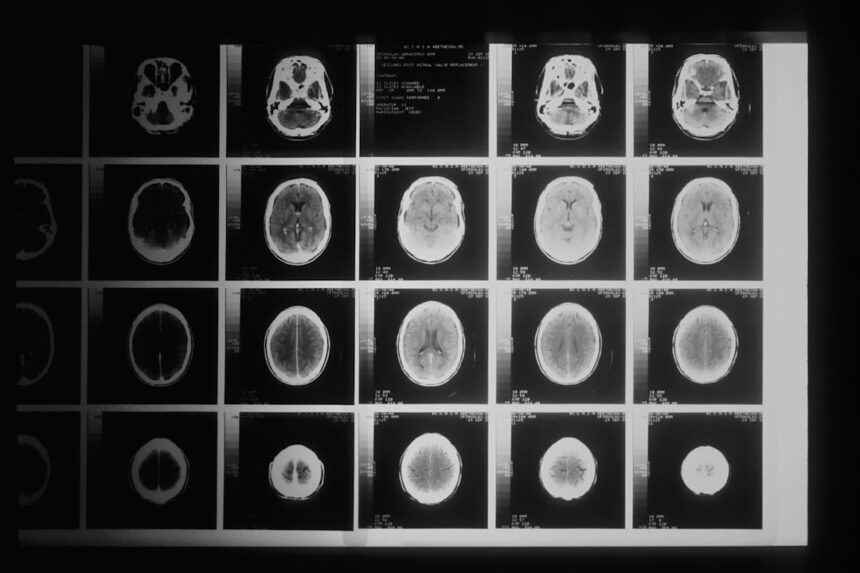

Your brain’s architecture is a testament to evolutionary design. Structures like the amygdala, often lauded as the seat of fear, play a crucial role in evaluating potential threats, both physically and socially. When confronted with uncertainty, the amygdala triggers a cascade of responses, releasing neurochemicals like cortisol that prepare your body for action – or, more often, for avoidance. This is not a malfunction; it’s a feature that historically kept your ancestors from becoming lion chow.

Think of your amygdala as your internal alarm system. It’s constantly scanning your environment, both internal and external, for anything that deviates from the norm or presents a potential danger. This could be anything from an unfamiliar loud noise to a challenging new task. The more novel or unpredictable an situation, the more likely your amygdala is to flag it as a potential risk, prompting a feeling of unease or anxiety. This is a signal, albeit an uncomfortable one, designed to make you pause and consider the potential consequences before committing.

While fear is a powerful motivator for avoidance, your brain also possesses a sophisticated reward system, primarily mediated by dopamine. However, it’s not just the magnitude of the reward that matters; it’s also the certainty of obtaining it. A small, guaranteed reward is often more appealing than a larger, uncertain one. This is because the anticipation of a sure thing triggers a reliable, albeit modest, dopamine release, creating a sense of satisfaction and reinforcing the behavior that led to it. This creates a positive feedback loop, subtly encouraging you to pursue paths where success is highly probable.